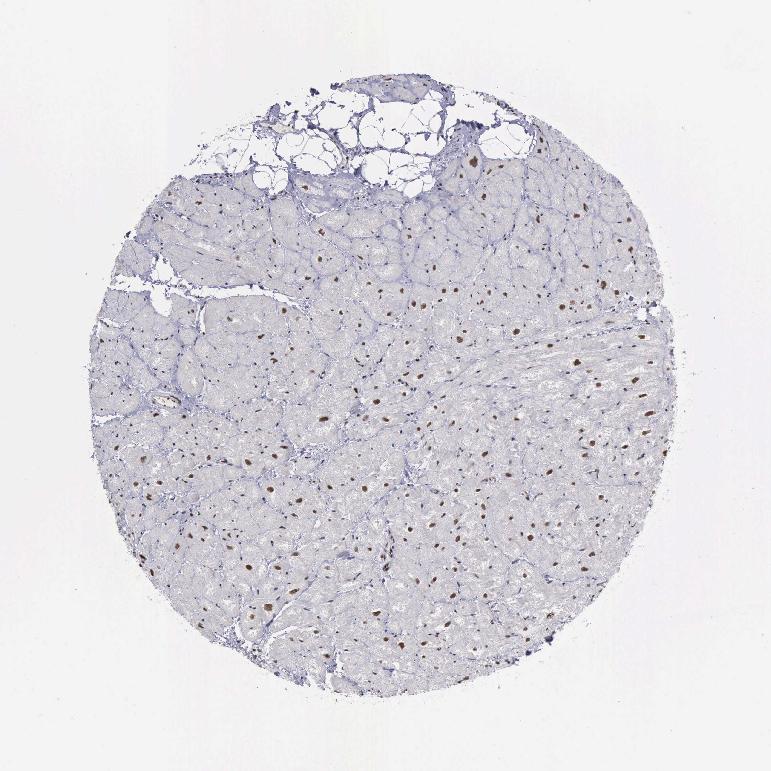

HEART MUSCLE - Antibody stainingi

Antibody staining in the annotated cell types in the current human tissue is reported as not detected, low, medium, or high, based on conventional immunohistochemistry profiling in selected tissues. This score is based on the combination of the staining intensity and fraction of stained cells.

Each image is clickable and will lead to virtual microscopy that enables deeper exploration of all samples and also displays staining intensity scores, fraction scores and subcellular localization as well as patient and tissue information for each sample.

Antibody HPA001119Antibody CAB009392

Cardiomyocytes MediumNot detected